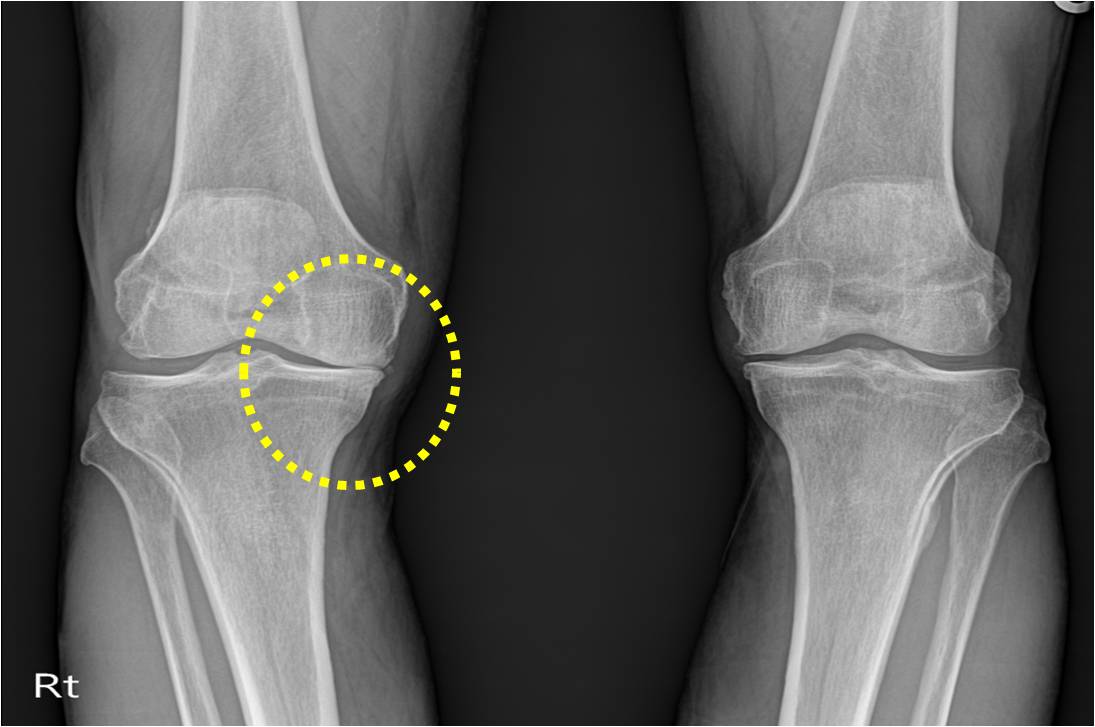

콘드로이친 효능 8. 골관절염

콘드로이친은 보통 골관절염 증상 관리를 위한 치료제로 사용되고 있어요. 미국에서 시행된 골관절염 환자 604명을 대상으로 한 연구에서 콘드로이친의 골관절염 통증에 대한 효과를 관찰했는데 그 결과, 무릎 골관절염 통증이 있는 사람들의 약 10%가 콘드로이친으로 인한 통증완화와 개선효과를 체험했다고 밝혔어요.

콘드로이친은 관절세포를 재생시키는데 도움을 주고 외부 충격을 흡수, 개선시키는데에도 뛰어난 효과가 있어요. 그러나 콘드로이친은 노화가 진행되면서 수치가 점점 저하돼요. 이는 곧 연골의 뼈와 뼈사이의 완충효과 또는 보호기능 약화로 이어지는 것을 의미하기 때문에 나이가 들수록 콘드로이친을 보충해 주는 것이 좋아요.

가장 잘 알려진 효능 중 한가지는 관절염 증상을 개선하고 치료하는 데 분비된다는 것인데요. 한 연구에서 무릎 관절염이 있는 참가자는 6개월 동안 황산 콘드로이틴을 계속해서 섭취한 결과 관절염 통증이 개선된 것으로 나타났어요

콘드로이친은 연골을 재생 및 복구하고 무릎이 받는 충격과 스트레스를 흡수해서 연골을 보호할 수 있어요. 반대로 콘드로이친이 부족하게되면 연골은 수분 보유력과 탄력을 잃게 되고, 연골이 계속 마모되면서 뼈끼리 마찰을 일으켜 관절염을 유발하기 쉽기 때문인데요.